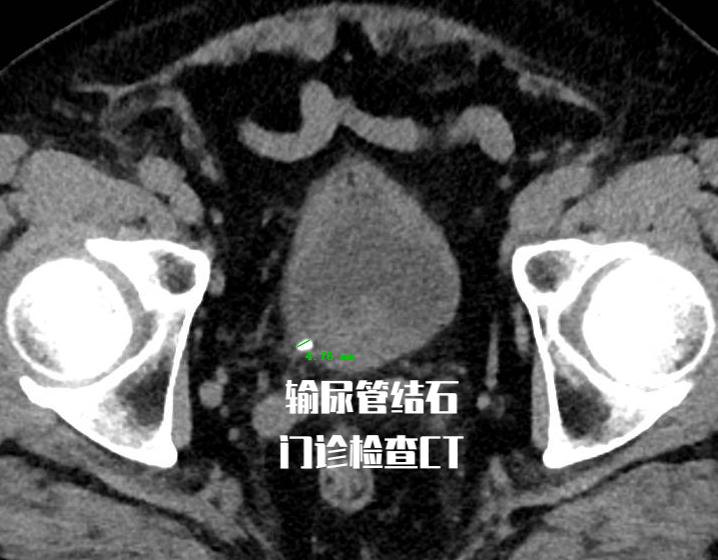

老王今年65岁,1周前因输尿管结石到门诊就诊, 做了CT检查提示结石位于输尿管末端,结石大小5mm。 根据他的结石大小和部位, 选择口服药物保守治疗,并嘱咐患者多饮水和加强活动。 但是1周时间过去了, 老王复诊时的CT提示他的结石仍然没有排出 。于是老王在昨天接受了输尿管镜下钬激光碎石术的治疗。